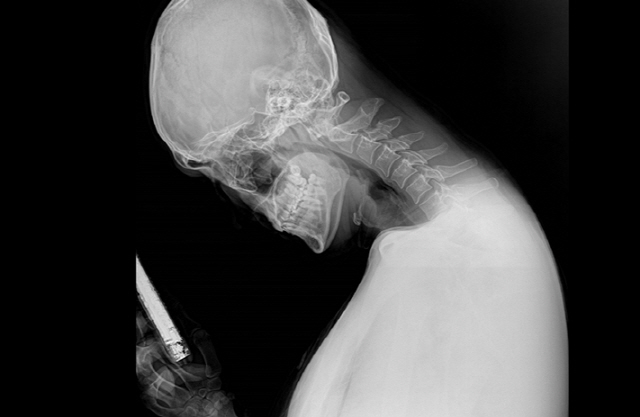

목을 길게 빼고 스마트폰을 보는 행동은 목디스크를 유발하기도 하며 심한 경우 근육통과 함께 허리디스크에도 안 좋은 영향을 준다.

이와 같은 증상이 발생했다면 X-레이와 척추 CT를 통해 목디스크인지, 후종인대골화증인지 확인하고, 정확한 원인에 따른 치료를 진행해야 한다.